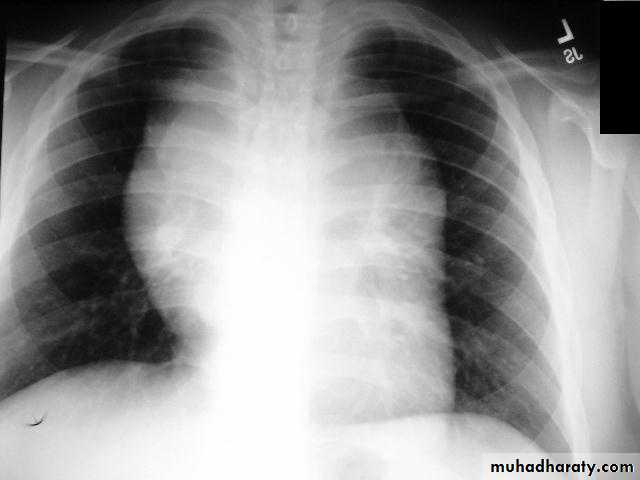

Pericardial effusions occur when fluid collects in the pericardial space (a normal pericardial sac contains approximately 30-50 mL of fluid).

Radiographic features

Plain radiographa very small pericardial effusion can be occult on plain film

there can be globular enlargement of the cardiac shadow giving a water bottle configuration known as Globe shape heart or pumpkin shape heart .

Pericardial effusion